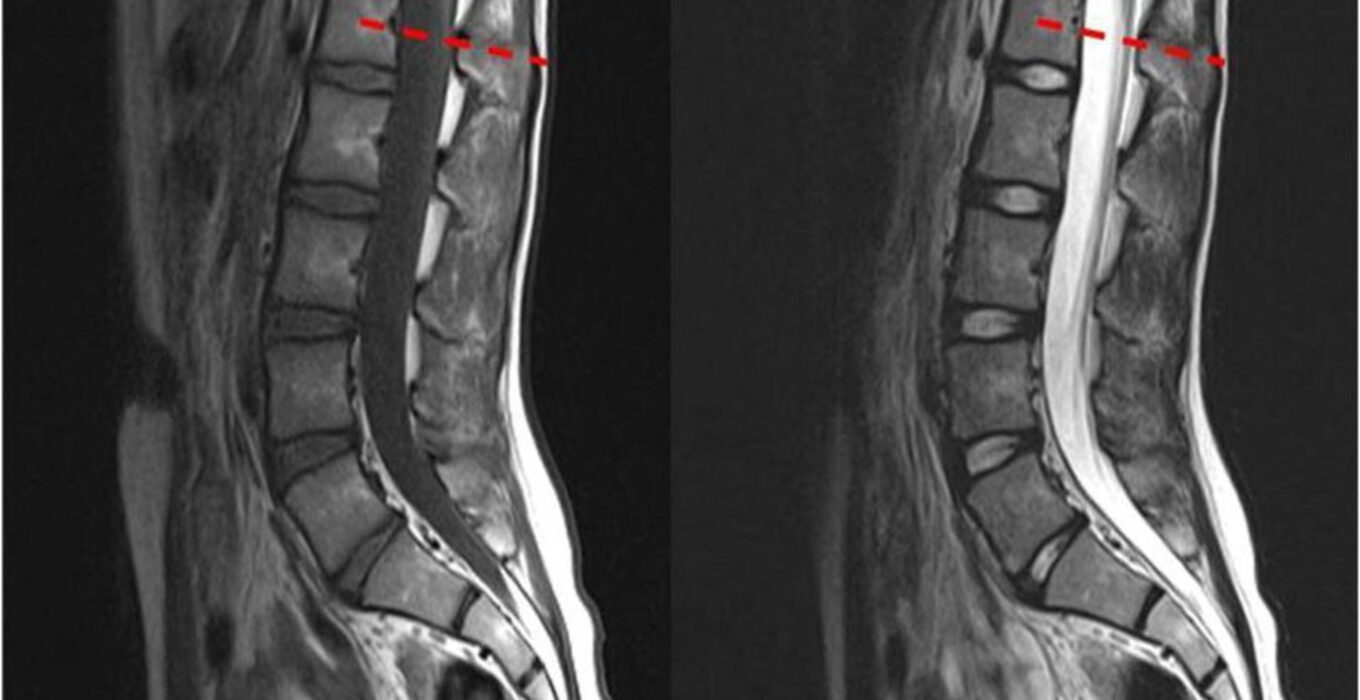

Синдром фиксированного спинного

Синдром фиксированного спинного 114 фото